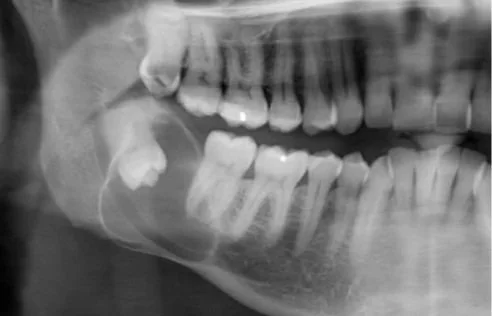

A large cyst attached to an unerupted wisdom tooth.

The decision to remove wisdom teeth is not automatic and is based on a careful clinical assessment. Dentists rely on dental examinations and panoramic radiographs to evaluate the position of the teeth, the presence of existing infections, and the likelihood of future problems. Extraction is generally recommended when there is evidence of disease, such as infection, cysts, or decay, or when damage to nearby teeth is likely. Preventative removal may also be advised for younger patients if the x-rays indicate a high probability of future complications, as the procedure and recovery are often simpler in late adolescence or early adulthood.